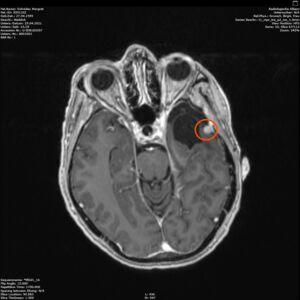

Am 03. November war mein Kontrollbesuch beim MRT. Leider ist ein kleiner Befund aufgetaucht. Schau das Video, dann kannst Du sehen.

Nun kann sich zeigen, ob die menschliche Medizin eine Lösung für mich hat. Möglichkeiten gibt es. Sogar mindestens eine, die der Neurochirurg als fein und elegant beschreibt. Gamma-Knife, eine Strahlentherapie. Klingt etwas nach Star Wars – man wird sehen,  etwas abwarten ist auch drin.

Heute war ich im MRT im Bremen. Der Befund des auswertenden Arztes ist, dass er der Meinung ist, dass der Tumor etwas gewachsen ist. Ich habe mir die Bilder angesehen und versucht diese Aussage zu verstehen. Vermutlich ist sie richtig, aber das Wachstum ist nicht heftig nur vielleicht von 0,7 cm auf 0,8 cm. Aber Gamma-Knife hat es offensichtlich nicht entfernt.

Zu meinem Geburtstag am 27.4. habe ich sehr schöne Geschenke bekommen und kann mich auch über meinen bunten Garten freuen, im Herbst gab es ein Tulpen-Sonderangebot, dem konnte ich nicht wiederstehen! Und nun ist das Ergebnis zu sehen. Am 28. April war wieder mal MRT-Termin. Leider hat es an dem Tag eine Vertretung des auswertenden Arztes gegeben, die Ärztin war super freundlich aber hat keine ganz konkreten Aussagen machen können, aber sie hat mir 2 CDs gebrannt, ich konnte eine gleich bei den Neurochirurgischen Ambulanz abgeben und eine mit nach Hause nehmen. Mein Blick auf die Bilder hat eine nazu unveränderte Lage gezeigt.

Heute war der Termin beim Chirurgen, leider schon um 9:00 Uhr und natürlich wollte ich die knapp 20 km mit dem Rad zurück legen, Stephan wollte gerne mitkommen. Leider war die bereits abgegebenen CD nicht eingelesen worden und so musste erstmal die Datenverarbeitung arbeiten und wir warten, bis wir eine Auskunft bekommen konnten. Fazit: Der bestehende Tumor ist kaum gewachsen. Aber es hat sich leider ein 2. Fund ergeben, sehr klein aber deutlich sichtbar. Aber Maßnahmen sind erstmal nicht notwendig.